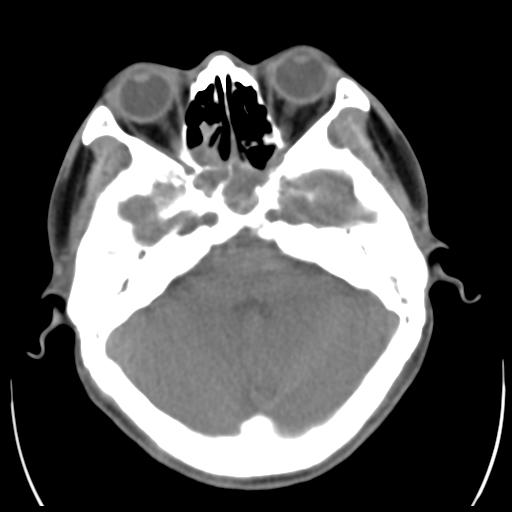

35m 鼻子时不时流血,头及右侧面部痛,颈部淋巴结未见明显大

软组织窗

考虑鼻咽癌侵犯颅底并突入右侧鼻腔;双侧中耳乳突炎。

蝶窦,后组筛窦及鼻咽部团块状软组织影,骨壁破坏,病变较广泛。考虑恶性肉芽肿。建议活检。

颅底骨质明显破坏 支持鼻咽癌 但病灶的边缘毛糙 不能除外炎性